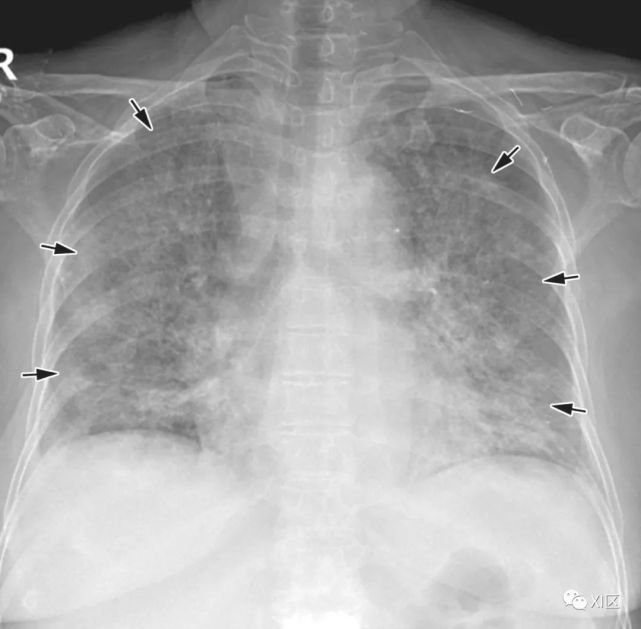

图8 20岁男子因腺病毒感染引起肺炎,伴有发热、咳嗽和呼吸困难。

(上) 最初的胸片显示左中下肺和右下肺区有不明确的斑片状实变和GGO(箭头)。同一天在叶间支气管水平(中)和肺下静脉水平(下)上获得的轴位胸部CT图像(厚度为5mm)显示不明确的斑片状GGO(箭头)和大叶实变(箭)。

Koo H J , Lim S , Choe J , et al. Radiographic and CT Features of Viral Pneumonia[J]. Radiographics, 2018, 38(3):719-739.